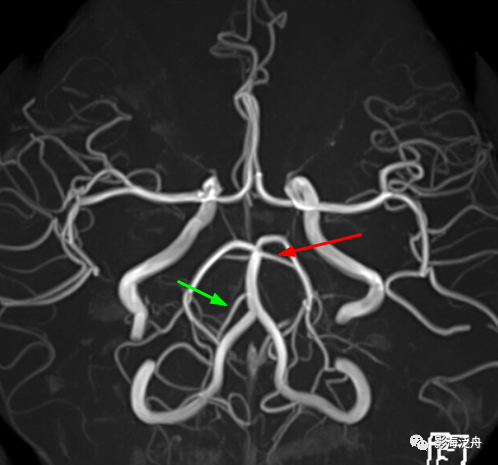

在MRA图上观察一下这三支动脉。如图所示,红箭:小脑上动脉;绿箭:右侧小脑下前动脉;小脑下后动脉未在图中显示(MRA中小脑下后动脉很少能显示出来)。